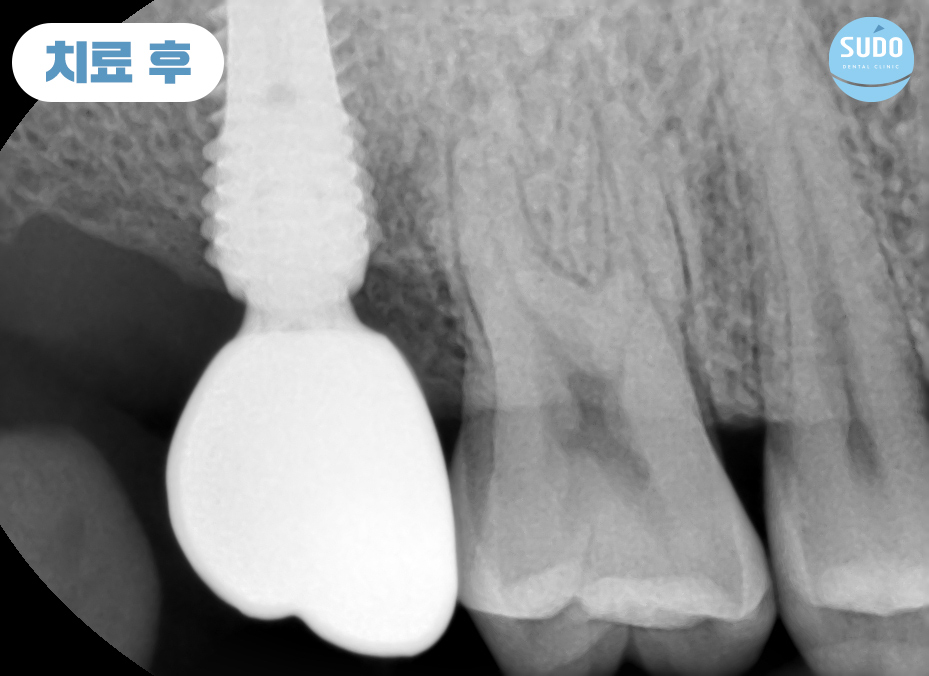

식립 당일 힐링 어버트먼트를 결합한 채로 본래의 잇몸뼈와 안정적으로 융합될 수 있도록 충분한 기간 동안 기다려주었습니다.

힐링 어버트먼트란, 임플란트를 보호하고 잇몸 조직의 적절한 치료를 촉진하며 미관을 개선하고 최종 보철물의 배치를 위한 안정적인 기준을 제공하기 위한 목적으로 사용합니다.

잇몸뼈의 융합을 위해 약 2개월 정도 기다린 후 영도임플란트치과 본원에서는 맞춤형 지대주 및 보철을 완성해 드렸습니다. 맞춤형 지대주를 사용할 경우 기성품으로 제작된 똑같은 크기와 모양의 지대주가 아닌 환자분들 개개인의 구강구조에 맞추어 제작한 것이므로 잇몸 라인에 맞춘 제작으로 틈이 생기지 않고 음식물 찌꺼기의 끼임을 방지해 주어 염증을 예방하는 효과가 있습니다.

또한, 지대주에 고정하게 되는 크라운에 균등한 교합력이 가해지기 때문에 쉽게 금이 가거나 파절되지 않고 유지력을 높여주어 부담을 줄여줄 수 있습니다.

최종 보철물을 장착하고 모든 과정을 마무리한 모습입니다.

임플란트를 단단하게 오랜기간 동안 사용하기 위해서는 인공치근과 잇몸뼈와의 융합이 매우 중요합니다. 잘 융합되어 단단하게 고정되어야 문제없이 사용이 가능하기 때문에 인공치근이 안정적으로 자리 잡을 수 있도록 기다려준 뒤 보철물을 장착합니다.

환자분께서는 잇몸뼈에 단단하게 고정된 임플란트로 편안한 식사에 만족도가 매우 높으셨으며, 주변 치아와의 크기와 색깔도 자연스러움에 감사의 인사를 전해주셨습니다.